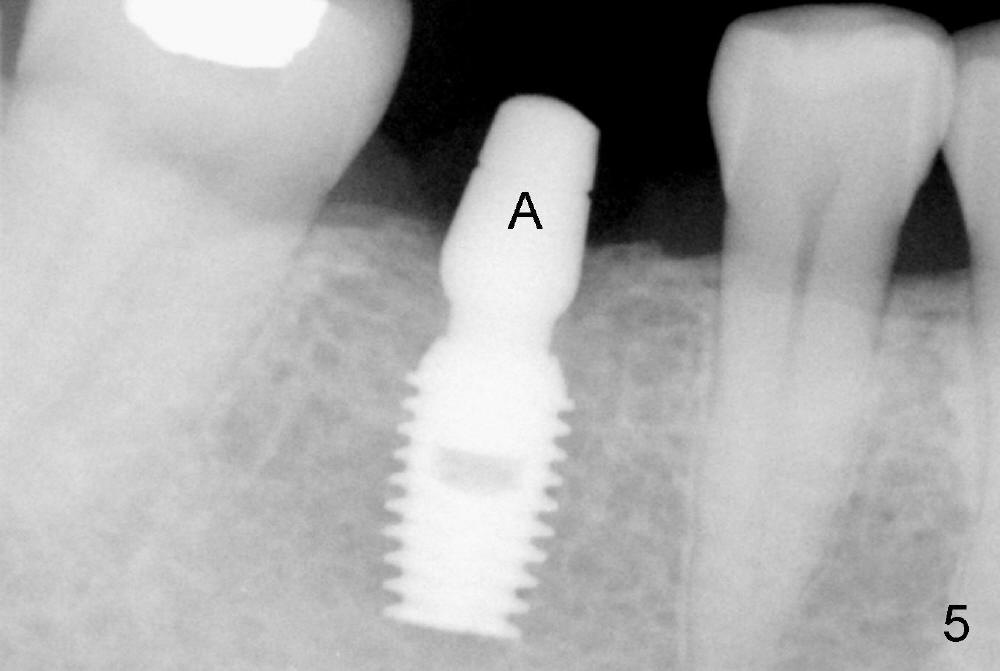

The abutment in Fig.5 (A) is angulated non-shouldered. There is no bone resorption. The crown margin will be close to the crest bone. To avoid retention of excess cement, the crown is cemented to the abutment extraorally (Fig.6).